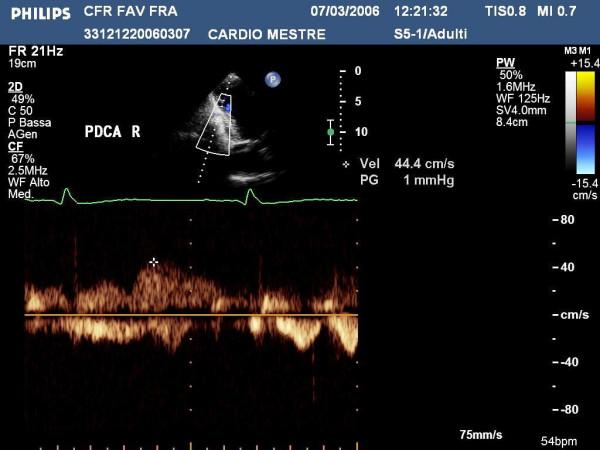

The aim of this paper is to highlight coronary investigation by transthoracic Doppler evaluation. This application has recently been introduced into clinical practice and has received enthusiastic feedback in terms of coronary flow reserve evaluation on left anterior coronary artery disease diagnosis. Such diagnosis represents the most important clinical application but has in itself some limitations regarding anatomical and technological knowledge. The purpose of this paper is to offer a didactic approach on how to investigate the different segments of left anterior and posterior descending coronary arteries by transthoracic ultrasound using different anatomical key structures as markers. We will conclude by underlining that, nowadays, innovative technology allows complete evaluation of both major coronary arteries in many patients in a resting condition as well as during pharmacology stress-tests, but we often do not know it.